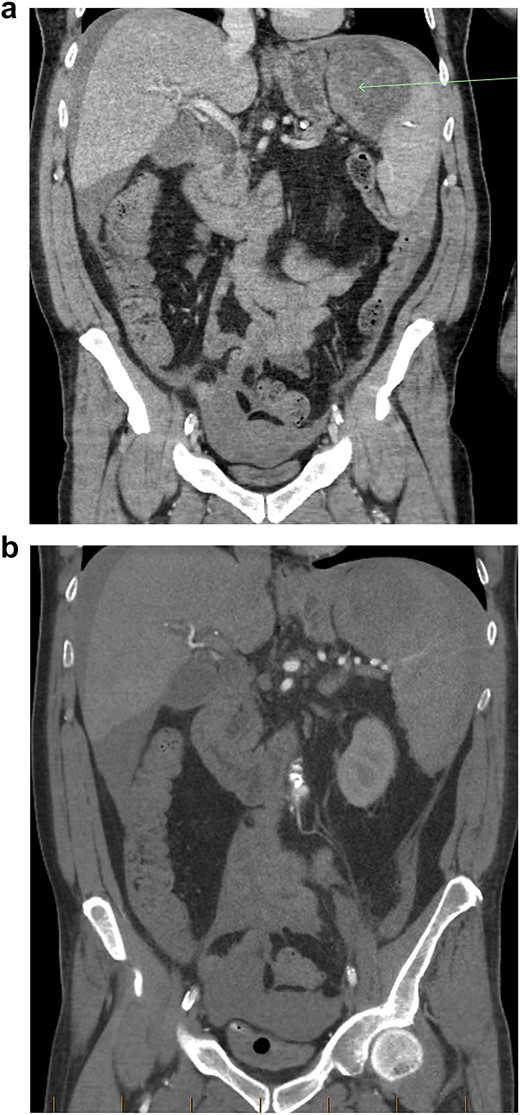

(a) Coronal view of CT-abdomen/pelvis in the portal venous phase showing moderate volume free-fluid/blood around the liver, both paracolic gutters, extending to the lower abdomen and pelvis. There is a large haematoma seen within or adjacent to the spleen (arrow). (b) Coronal view of CT-abdomen/pelvis angiogram redemonstrating the known splenic haematoma, however there was no evidence of active arterial contrast extravasation.

The patient responded well to intravenous (IV) fluid resuscitation. Urgent surgical and intensive care reviews were attended. It was determined that the cause for the patient’s presentation was spontaneous splenic rupture, likely secondary to occult haematological malignancy, complicated by tumour lysis syndrome, as well as anuric acute renal failure. A subsequent CT-angiogram was urgently obtained, which did not reveal and active splenic contrast extravasation. Interventional Radiology was consulted from the regional tertiary facility, whom advised that no intervention could be offered in the absence of contrast blush to indicate active bleeding. Given that the patient was responsive to fluid resuscitation, multi-disciplinary decision was that the patient should be medically optimized with dialysis before pursuing surgical intervention, and he was subsequently admitted to intensive care for monitoring. Within 3 hours of admission however, the patient became progressively shocked, with an acute drop in haemoglobin (88 to 61 g/L) as well as platelet count (90 to 63 × 10^9 /L). An emergency laparotomy/splenectomy was performed overnight. Intra-operatively there was large volume free blood and clots within the abdominal cavity. There was a large capsular tear of the superior pole of the spleen (Fig. 2a and b), and total splenectomy was performed. Total estimated blood loss was 4.5 L. He received a total of 5 L of crystalloid, 8 units of packed red blood cells, 1 g tranexamic acid, 1 unit of platelets, 6 units of cryoprecipitate, 2 units of fresh frozen plasma, as well as 1.3 L of cell-saver blood.